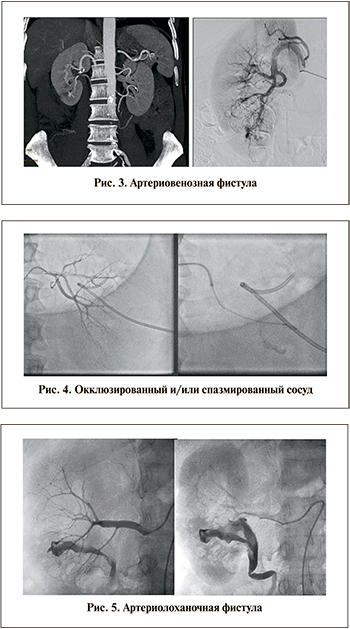

- артериовенозные фистулы. Могут сохраняться по прошествии дней и недель после повреждения почки. Служат источником кровотечений и макрогематурии (рис. 3);

- окклюзированные и/или спазмированные сосуды. Чаще всего подобное состояние сосудов вызвано повреждением или полным их разрывом с последующим тромбозом. После нормализации давления или его повышения кровотечение из таких артерий может рецидивировать, поэтому они подлежат эмболизации (рис. 4);

- артериолоханочные фистулы (рис. 5).